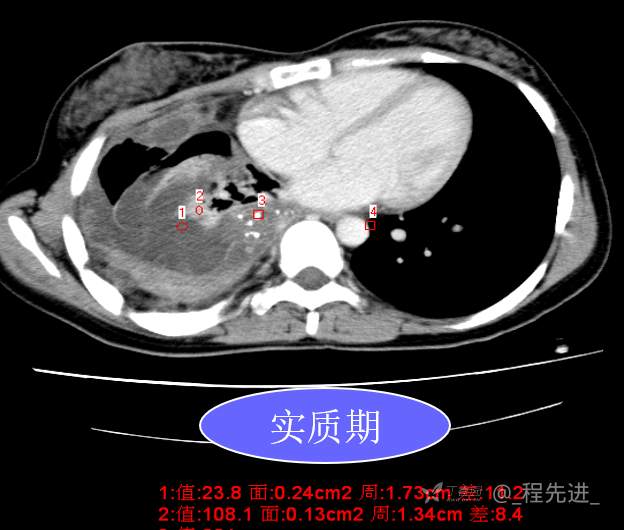

患者性别:女

患者年龄:26岁

简要病史:反复胸闷、气喘、咳嗽半年